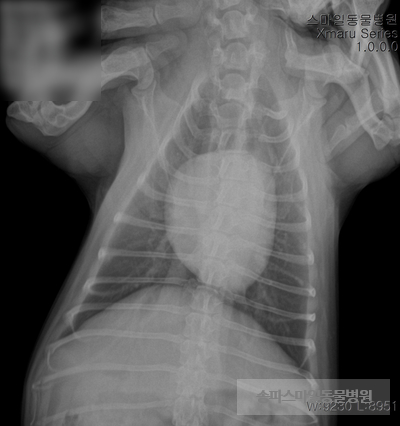

초음파 검사상 자궁의 크기가 매우 확장되었으며 자궁 내부의 액체가 고여있는 것으로 확인되었습니다.

강아지 자궁축농증이 진단되었습니다.

수액처치후 “ㄹ” 긴급수술 하였습니다.

수술은 안전하게 마무리되었습니다.

자궁 내부는 곪아 있었습니다.